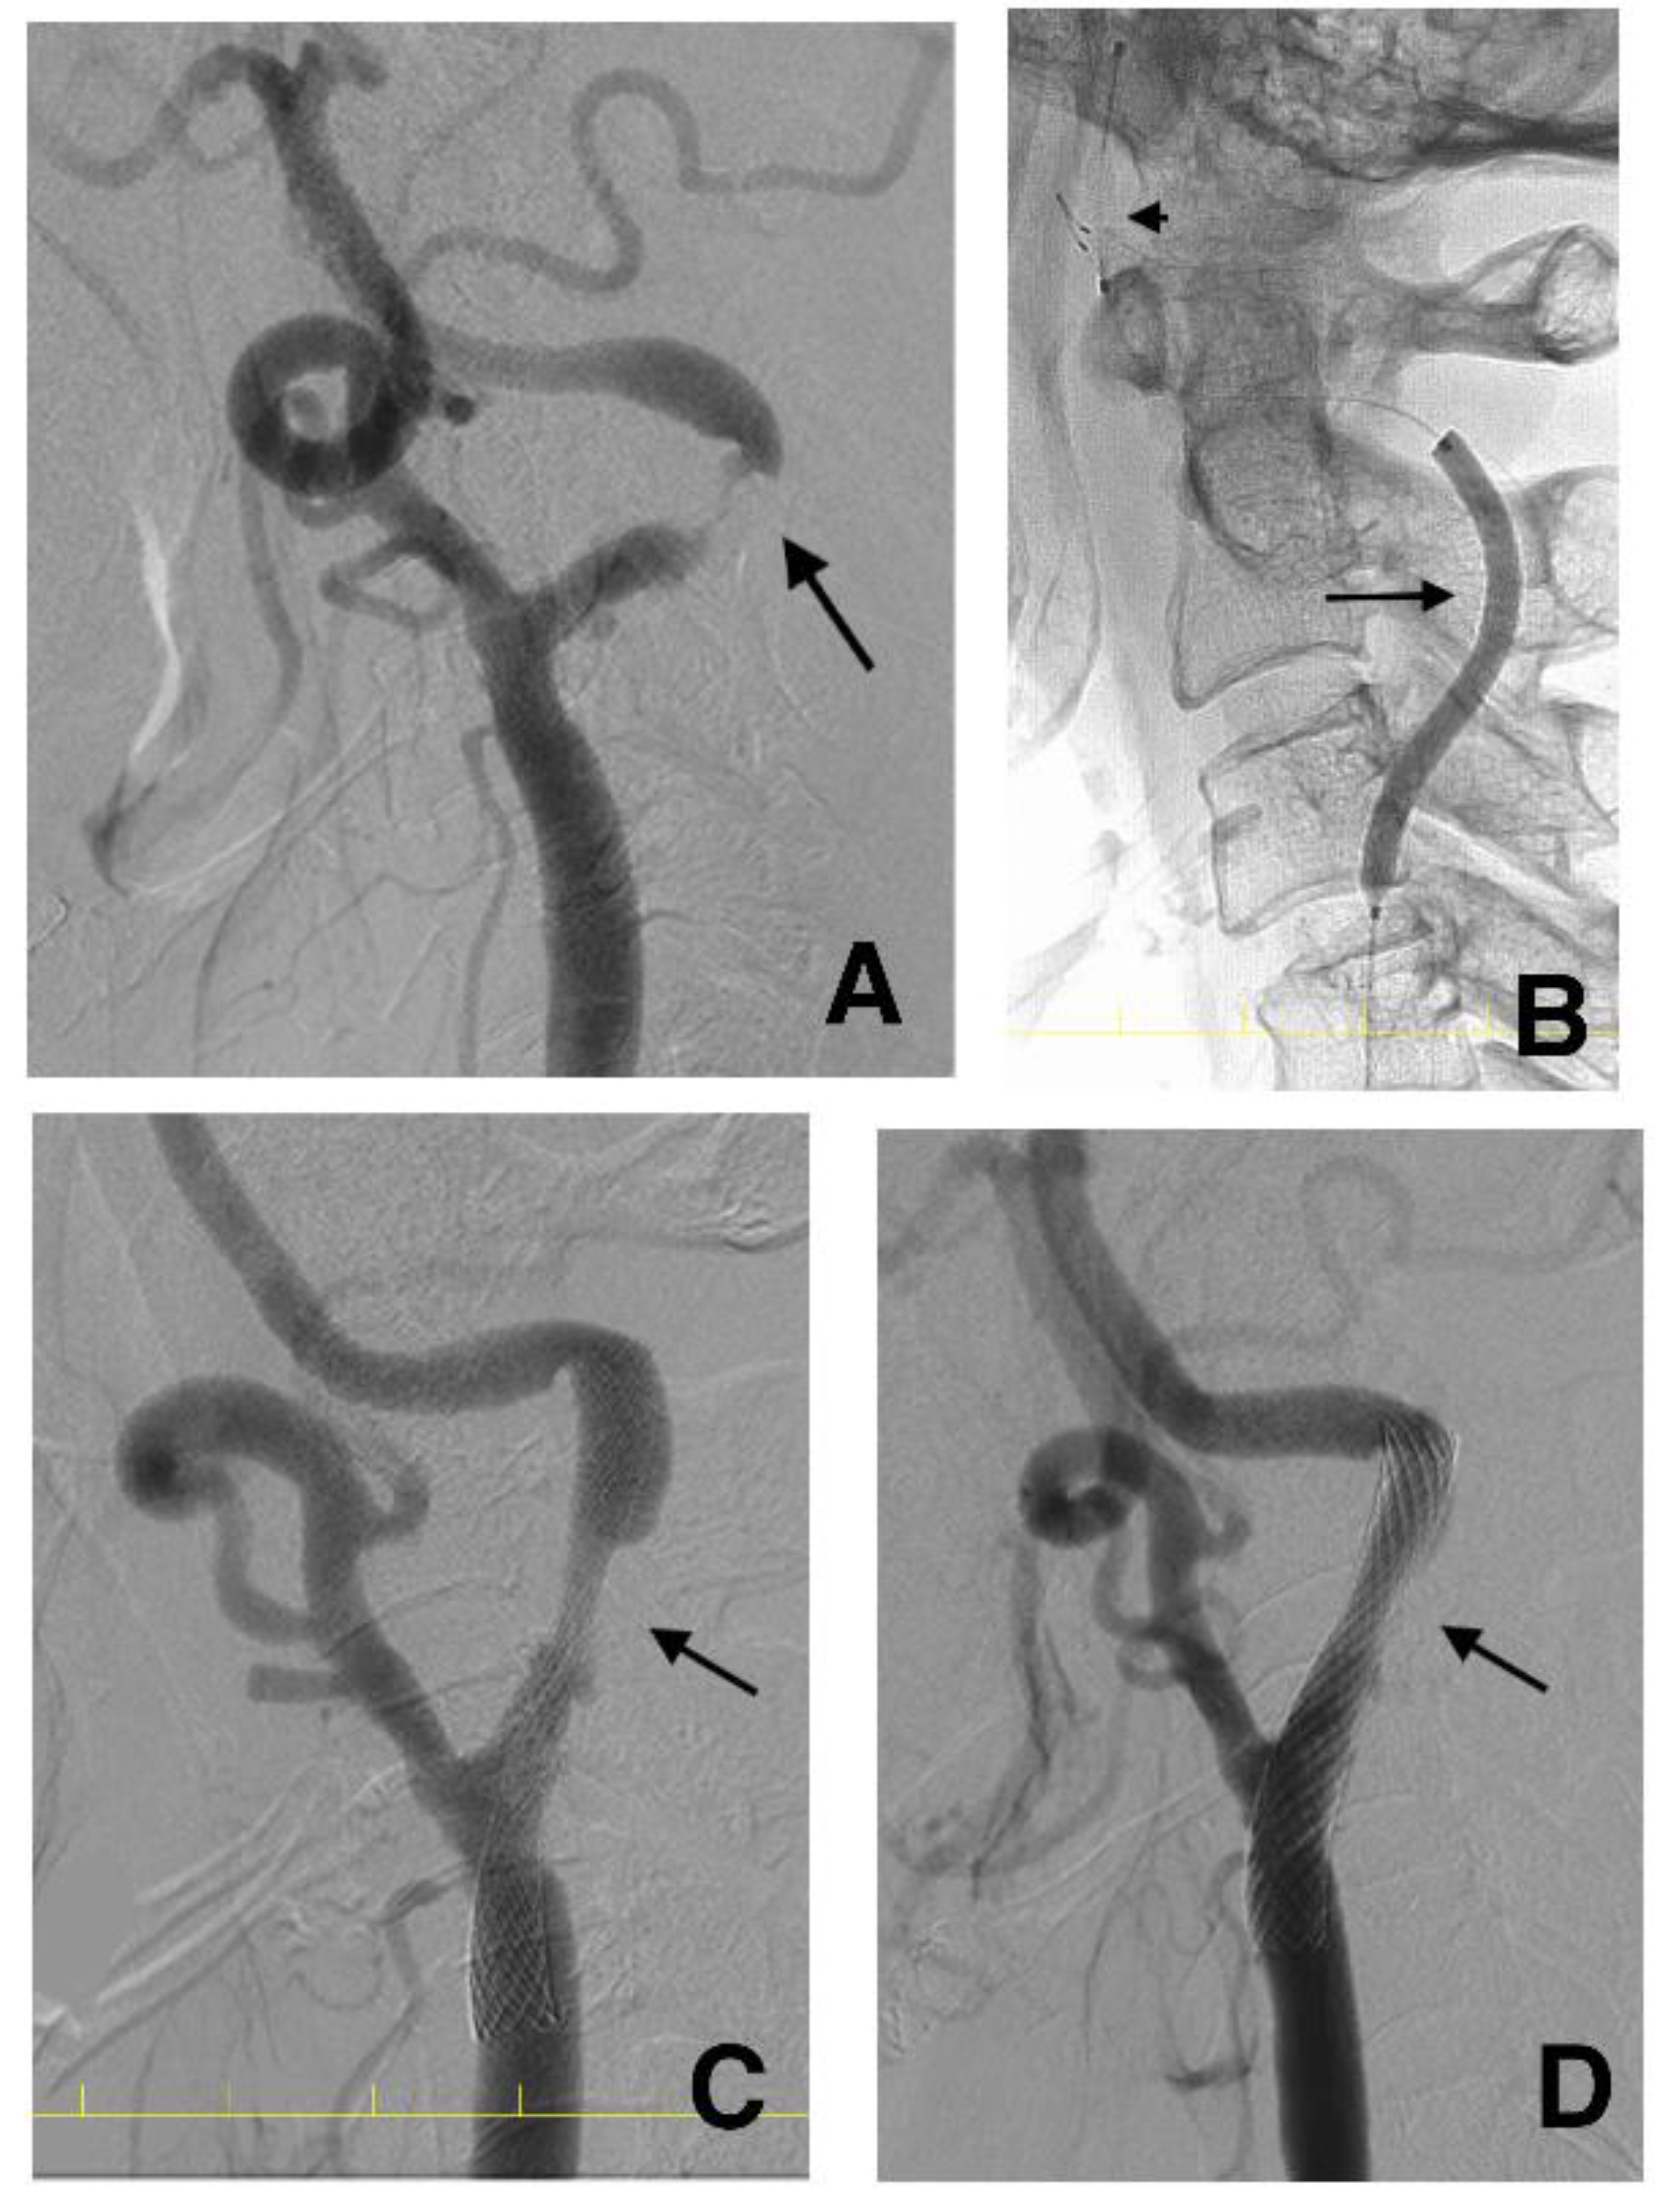

2.6. CAS Procedure

2.7. DSA Investigation after CAS